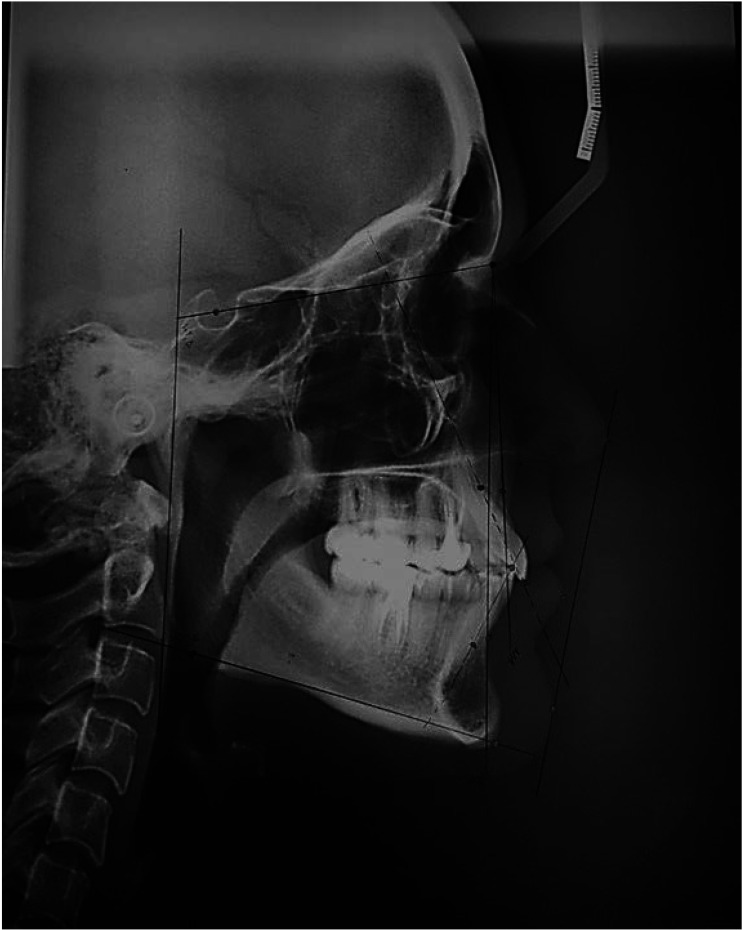

Purpose: The aim of this study was to compare the accuracy of AI-based AudaxCeph software, Dolphin software, and the manual technique for identifying orthodontic landmarks and tracing lateral cephalograms.

Materials and methods: In this cross-sectional study, 23 anatomical landmarks were identified on 60 randomly selected lateral cephalograms, and 5 dental indices, 4 skeletal indices, and 1 soft tissue index were measured. Each cephalogram was traced using 4 different methods: manually, with the Dolphin software, with the AudaxCeph software automatically, and with the AudaxCeph software in semi-automatic mode. The intra-class correlation coefficient (ICC) and Bland-Altman plots were used to evaluate the agreement between methods. Inter-observer and intra-observer agreements, calculated using the ICC, confirmed the accuracy, reliability, and reproducibility of the results.